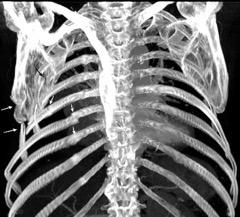

Signos radiológicos TC

Hallifax RJ et al. State-of-the-art: Radiological investigation of pleural disease Respiratory Medicine 2017

Nivel hidroaéreo o burbujas

Forma lenticular o elíptica Ángulos obtusos

> Grasa Extrapleural (60-80%)

Situación no gravitacional (no siempre)

Compresión de estructuras pulmonares

Límite muy bien definido Tabicación

Engrosamiento de la pleura parietal 36/ 59 exudados (61%) 56% de D. paraneumónicos 100% de empiemas Especificidad.. 96%.

Exudado versus trasudado.

Aquino SL, et al. Pleural exudates and transudates: diagnosis with contrast-enhanced CT. Radiology 1994

Signo de la Pleura separada “Split pleural sign”

Capas pleurales de grosor uniforme realzadas por el contraste

No específico de empiema. Indica “exudado”. 68% de pacientes con empiema pleural.

Capas pleurales de grosor uniforme

Realce grasa extrapleural (30%)

> Grasa Extrapleural. (60-80%)

Kraus GJ. Split pleural sign. Radiology 2007